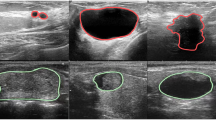

The segmentation results of these methods for the same image are shown in Fig. 8. As shown in the figure, on images with low noise, all methods give satisfactory segmentation results. However, on images with strong noise and unclear tumor boundaries, the segmentation results of the other methods decrease substantially, whereas the proposed method exhibits a smaller decline and maintains high segmentation accuracy, demonstrating stronger robustness.